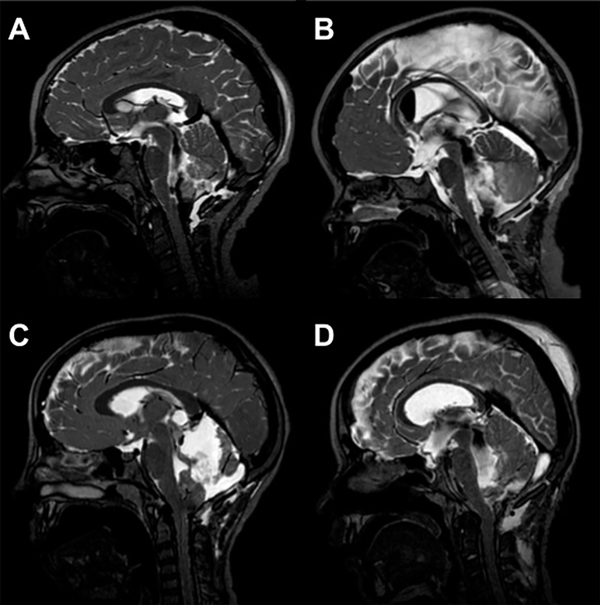

La obstrucción de salida del IV ventrículo se interpretó como la ausencia de comunicación de LCR (permeabilidad) en imágenes de RMI entre el IV ventrículo y la cisterna magna (Figura 2).

Figura 2: Imágenes de RM sagitales ponderadas en T2 drive, de cuatro postoperatorios de resección tumoral de fosa posterior. En A y B se evidencia vacío de flujo entre IV ventrículo y cisterna magna. En C y D se observa la ausencia de comunicación de LCR (permeabilidad) entre IV ventrículo y cisterna magna.